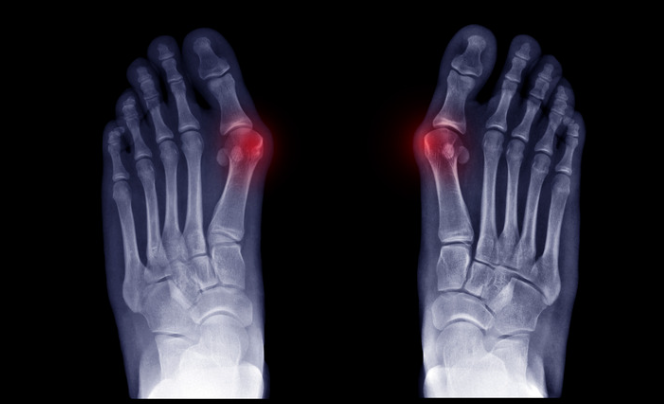

外反母趾による痛みや変形を愁訴に整形外科外来を受診する患者は,年々中高年の患者のみならず小児から高齢者まで年齢的にも幅広く受診しています。3年に1回行われる厚生労働省の患者調査では,1984年(昭和59年)のデータを基準として外反母趾患者統計を比較すると,2011年(平成23年)では外来受診は7倍に増加しました。さらに2017年(平成29年)では外来受診は13倍に増加しています。その理由としては、疫学的に患者の90%を占める女性が社会の第一線で活躍する場が多くなったこと,そして足に対する美容や整容に対する意識が高まったことなどがあげられます。

わが国では外反母趾角20°以上が外反母趾と定義され,その症状は第1中足骨頭が内側に突出した部分(バニオン)の痛みや趾神経障害にとどまらず,基節骨の外転・回内の結果,爪縁が地面や第2趾と接触して生じる爪周囲炎,crossover toe変形での機械的刺激や第2,3趾槌趾,第2,3中足骨頭下の胼胝,あるいは転倒リスクの増大など多岐にわたります。

外反母趾の診断

診断はある程度見た目でできます。診察では痛みの場所や魚の目の場所、偏平足がないかなどを確認します。またレントゲンを撮ることで外反母趾の重症度をチェックします。